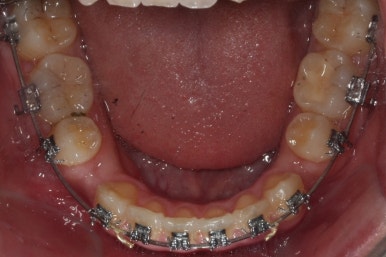

이제 가지런하게 하는 작업은 거의 종료되었고, 향후의 과정은 남은 이 뽑은 자리를 당겨주어 틈을 없애주면서도 입도 뒤로 좀 넣어주는 것이 되겠습니다.

위아래 아주 단단한 철사로 지탱해주면서 (앞니쪽에 고리가 달린 철사) 앞-뒤 치아를 서로 당겨주면서 이 뽑은 자리를 서서히 없애줍니다.

틈새를 모으는 작업을 반복적으로 행해주면 얼핏 봐서는 이뽑은 줄 모르게 치아가 서로 붙어있는 상황이 됩니다.

이제 이 뽑은 자리는 충분히 다 닫혔고, 틈새가 다시 벌어지지 않는지를 몇 개월에 걸쳐 확인한 뒤 그동안 디테일한 마무리 과정을 해주게 됩니다.